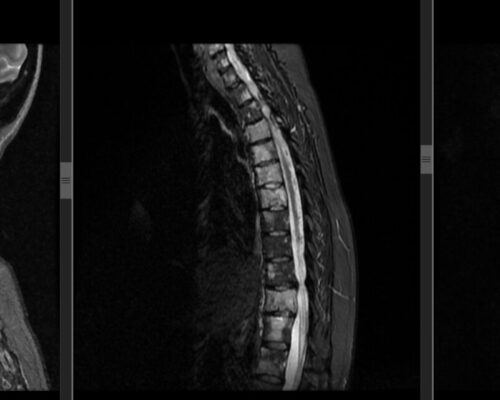

Hernia de disc lombară recidivată este o cauză frecventă de durere persistentă după intervenții chirurgicale ale coloanei. Acest caz evidențiază beneficiile unei abordări moderne, minim invazive, în tratamentul acestei patologii complexe. Contextul pacientului Pacientul este un bărbat activ, în vârstă de 35 de ani, din București, cu antecedente de intervenție chirurgicală lombară. Deși inițial a […]